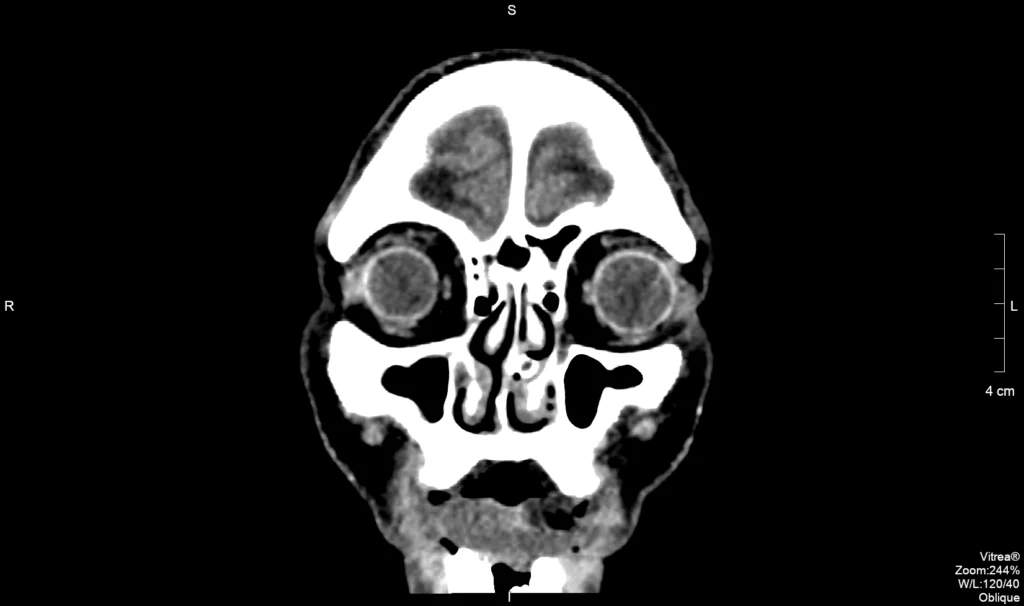

Figura 1: Cortes axiais de TC de crânio mostrando estruturas anatômicas principais

Anatomia da Órbita

A órbita é uma estrutura complexa formada por múltiplos ossos e contendo estruturas nobres como o globo ocular, músculos extraoculares e nervo óptico. A TC é o método de escolha para avaliação de trauma e patologias orbitárias.

Figura 2: Corte sagital de TC de órbitas mostrando estruturas anatômicas